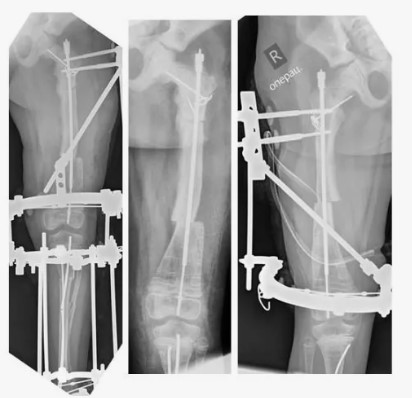

Рентгеновские снимки:

- Рентгеновские снимки могут показать характерные особенности НО, включая тонкие и хрупкие кости, аномальные изгибы костей и наличие переломов в анамнезе.

Ортопедические вмешательства:

- В некоторых случаях могут потребоваться операции для исправления деформаций или установки металлических стержней для стабилизации костей, особенно после переломов.